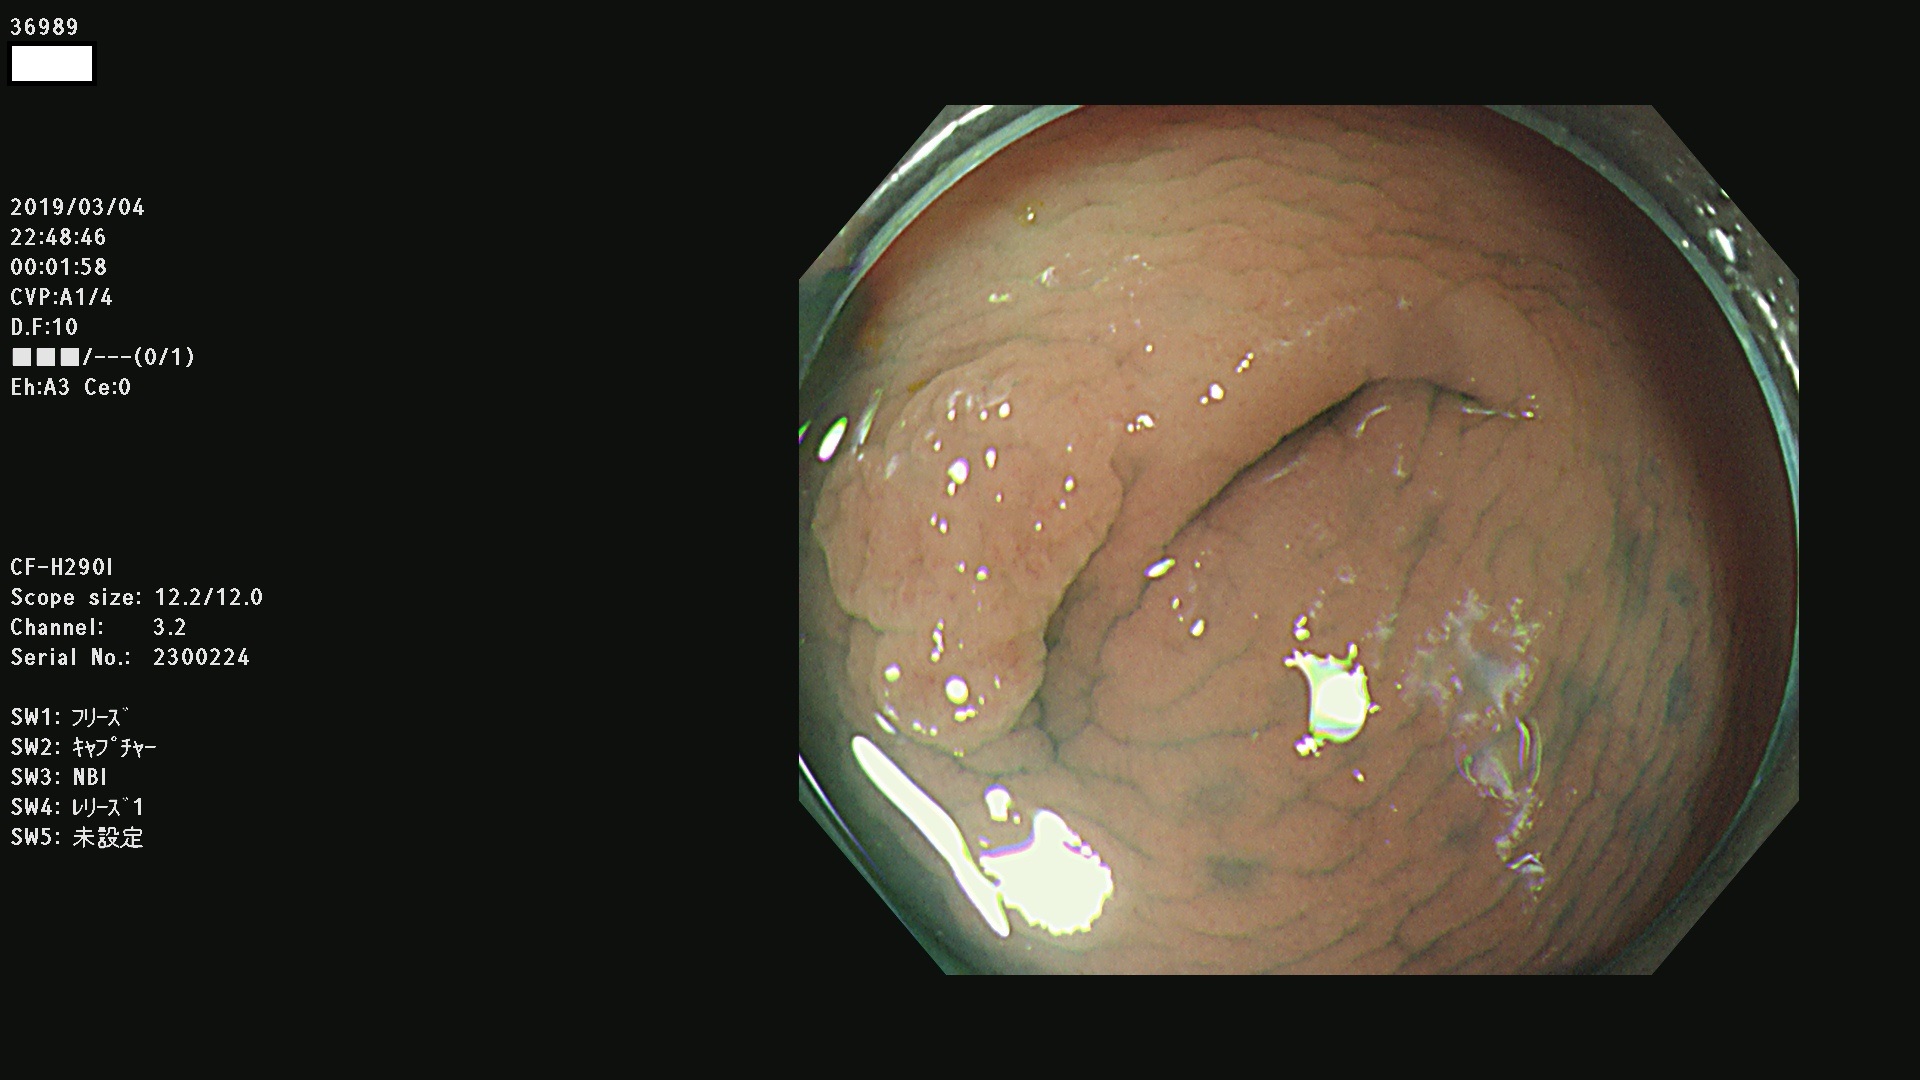

腺腫発見率 67 % (カルテ番号 36900〜36999の100名の方の検査結果で集計)大腸癌検診最新情報

以下のカルテ番号の方に腺腫(Adenoma,Group3〜5)が見つかりました(集計法)

36900 36901 36903 36904 36905 36908 36909 36910 36911 36913 36914 36915 36916 36917 36918 36919 36920 36923 36924 36925 36927 36928 36930 36931(SSAPのみ) 36933 36935 36936 36937 36941 36943 36944 36945 36946 36949 36951 36953 36954 36955 36957 36963 36965 36966 36967 36968 36969 36970 36974 36975 36976 36977 36978 36979 36980 36981 36983 36984 36986 36987 36988 36989 36990 36991 36993 36994 36996 36998 36999

発見困難で危険性の高い平坦型病変(上記100名より抽出) ![]()